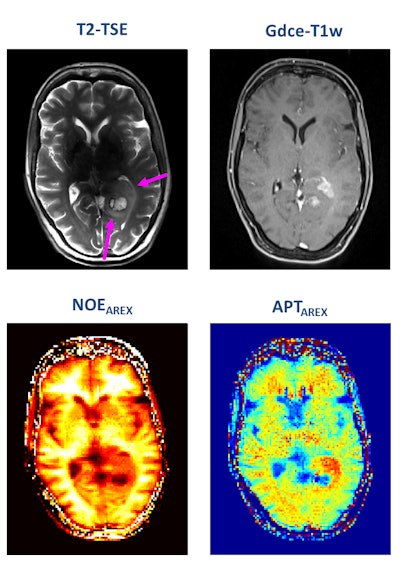

Turning to some of the newer imaging methods, he mentioned that chemical exchange saturation transfer (CEST) imaging is showing promise because it allows for the measurement of protein content in the tumor.

"Change in protein content is important. We don't fully understand the biological significance of this, but we have seen meaningful changes, particularly in brain tumors," he noted. "We've also seen a genetic mutation that results in a measureable difference in protein content. We hope that in time we will use CEST for other applications."